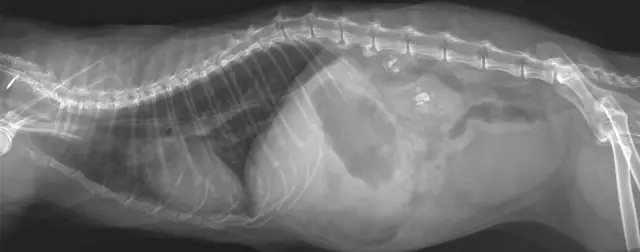

Письменное информированное согласие на публикацию данного дела было получено от пациента. Мужчина 56 лет (рост 165 см; вес 70 кг) без значительного медицинского анамнеза обратился в отделение неотложной помощи с жалобами на боль в правой груди, застой в груди и одышку после получения тупой травмы правой груди. Его жизненные показатели были следующими: частота сердечных сокращений (ЧСС), 91 уд / мин; частота дыхания (ОР), 34 вдоха / мин; артериальное давление (АД), 108/71 мм рт.ст.; и начальная пульсовая оксиметрия насыщения (SpO 2) 85%. Газ артериальной крови: рН 7, 35, ПаСО 2 47 мм рт. Ст. И ПаО 2 49 мм рт. Хрипящая грудь и парадоксальное дыхание были очевидны. Значительная подкожная эмфизема в области шеи и передней части груди была диагностирована с выраженным крепитацией. Компьютерная томография (КТ) показала массивную подкожную эмфизему, пневмомедиастинум, множественные переломы ребер, двусторонний гемопневмоторакс и компрессионный пневмоторакс (рис. 1 а и б). Было замечено смещение сочленения грудины, и стернальная часть правого первого ребра проникла через заднюю стенку трахеи над килем (рис. 2). Грудная трубка была вставлена для декомпрессии пневмотораксов и гемопневмоторакса, и проблемы с дыханием были облегчены. К сожалению, быстрое ухудшение подкожной эмфиземы указывало на постоянную утечку воздуха через разрыв через 3 часа. У пациента развился респираторный дистресс и он стал гемодинамически нестабильным. Эмерджентная КТ показала, что правое первое ребро проникло через заднюю стенку трахеи примерно на 6 см ниже голосовой щели и на 6 см выше киля (рис. 3а). Первое ребро разделило трахею на две части: 5, 3 мм в диаметре слева и 6, 6 мм справа (рис. 3, б и в). Пациент был быстро переведен в операционную. Он был взволнован, при дыхательной недостаточности и его жизненные показатели были: ЧСС 108 уд / мин; 30 вдохов в минуту; BP 90/58 мм рт.ст. и SpO 2 80%. Мы поддерживали гемодинамическую стабильность с помощью внутривенного фенилэфрина. Фиброоптический бронхоскоп был сразу же доступен с эндотрахеальными трубками разных размеров. Общая анестезия была индуцирована мидазоламом 2 мг, фентанилом 0, 05 мг и 2% ~ 5% севофлюраном при сохранении спонтанной вентиляции. Стерильный гибкий волоконно-оптический бронхоскоп, загруженный 5, 5 мм эндотрахеальной трубкой (наружный диаметр 7, 3 мм), идентифицировал разрыв трахеи, и эндотрахеальная трубка была продвинута дистально мимо места разрыва. Он самопроизвольно дышал с фракцией вдыхаемого кислорода 100%, дыхательным объемом 330 мл, частотой 30, SpO 2 95% и парциальным давлением конечного прилива двуокиси углерода (PetCO 2) 40 мм рт. Глубина анестезии поддерживалась до достижения показателя биспектрального индекса 40-60. Хирургическая бригада открыла грудную полость, чтобы обнажить правое первое ребро, а правое первое ребро было удалено примерно через 30 минут (рис. 4а). Эндотрахеальную трубку диаметром 7, 5 мм затем заменяли и располагали дистально до разрыва под руководством гибкой бронхоскопии. После подтверждения расположения эндотрахеальной трубки внутривенно вводили цисатракурий 14 мг и фентанил 0, 15 мг. Пациенту была проведена искусственная вентиляция легких с интервалом положительной вентиляции. Респираторные параметры были следующими: фракция вдыхаемого кислорода 60%, дыхательный объем 550 мл, частота 12, пиковое давление в дыхательных путях 22 см H 2 O, SpO 2 98% и PetCO 2 38 мм рт. Непосредственное хирургическое восстановление разрыва трахеи было успешным, и он был переведен в отделение интенсивной терапии. В отделении интенсивной терапии ему управляли на вентиляторе с синхронизированной прерывистой принудительной вентиляцией и постоянным положительным давлением в дыхательных путях. Для улучшения легочной функции на 5-й день после первой операции были выполнены плановые хирургические операции по восстановлению перелома грудины, множественных переломов ребер и гемопневмоторакса под общей анестезией, а у пациента был экстубирован на 7-й день после операции. Повторная КТ продемонстрировала целостность стенки трахеи (рис. 4 б). Комплексная реабилитация проводилась в течение 2 недель, и он был выписан домой в послеоперационный день 41.

фигура 1

КТ грудной клетки, показывающая массивную подкожную эмфизему, пневмомедиастинум, множественные переломы ребер, двусторонний гемопневмоторакс и компрессионный пневмоторакс на легочном (а) и средостенном (б) окнах